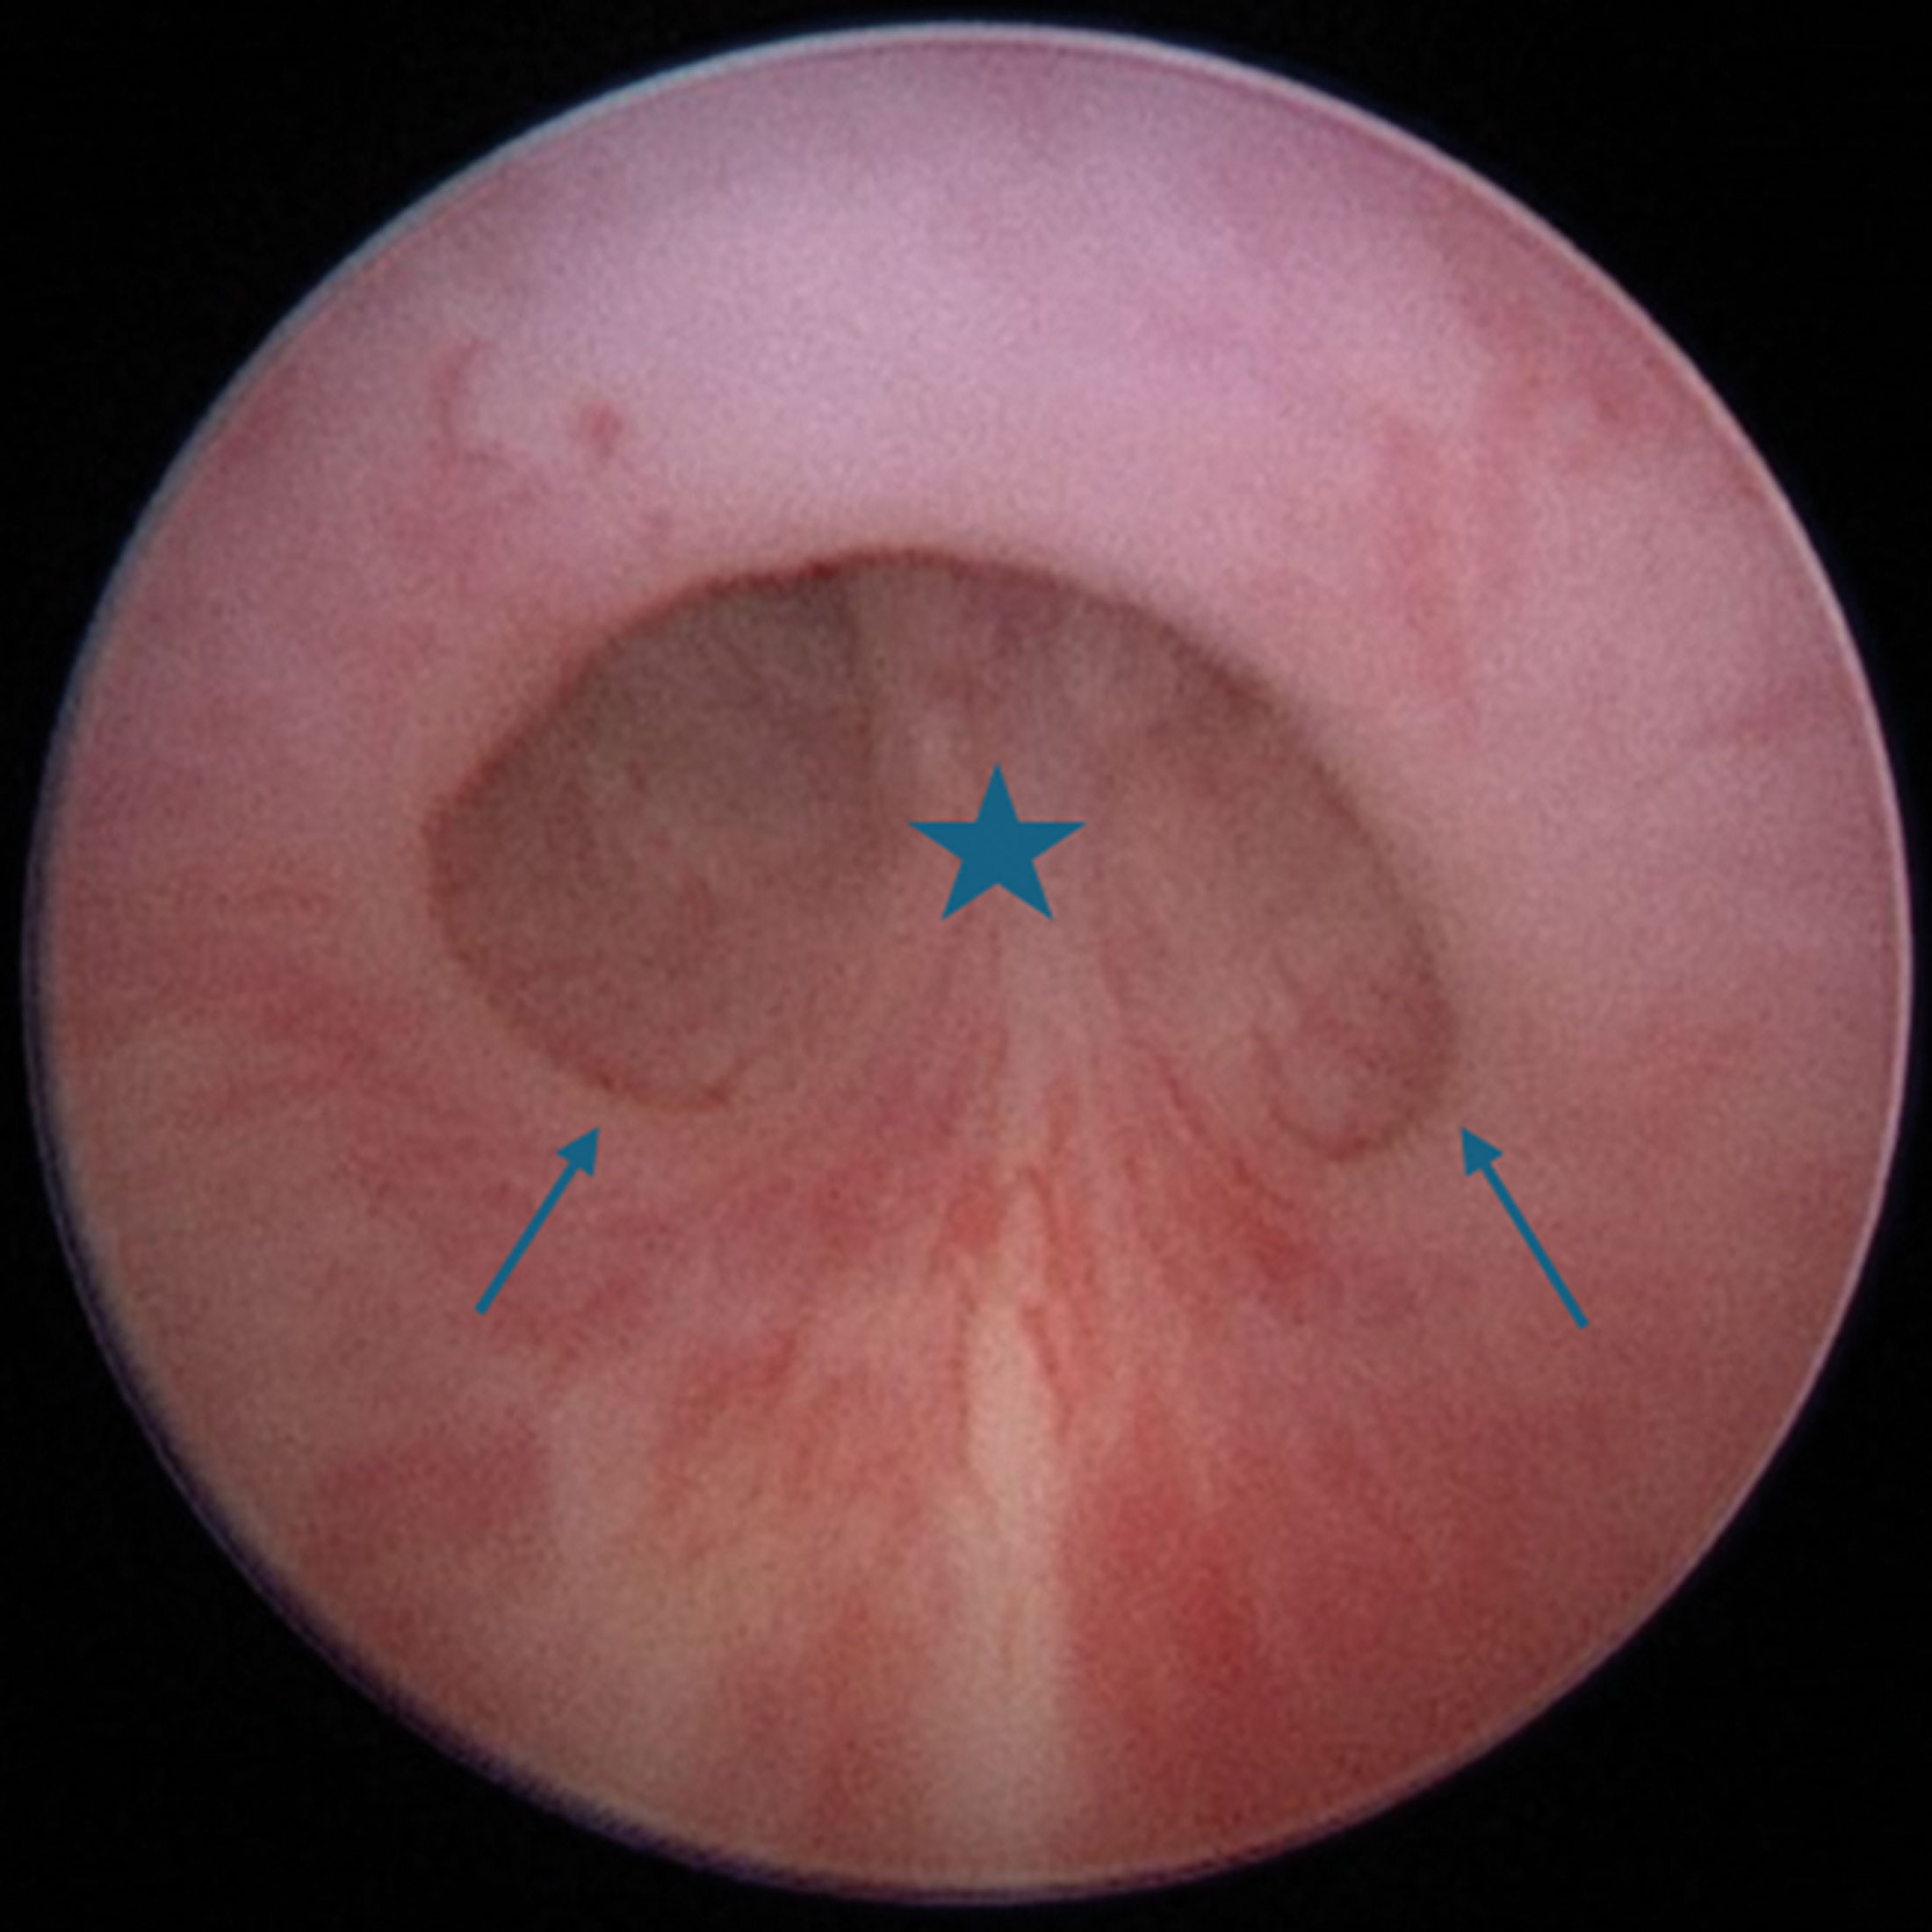

Figure 3: Endoscopic view of PUV: flaps (arrows) that arise from base of verumontanum (star).

On rigid cystoscopy, signs to look for include: i) dilated posterior urethra, ii) high bladder neck, and iii) trabeculated bladder wall. The valves appear endoscopically as flaps extending distally from the base of the verumontanum to each side wall of the prostatic urethra (Figure 3). Our recommendation is to assess the presence of PUV carefully both with anterograde and retrograde movement of the cystoscope. The degree of bladder filling, the pressure of irrigation-flow, and the experience of the surgeon can result in significant inter-observer variability, which is more profound in subtle cases. A study showed lack of consensus even among experts in detecting PUV on endoscopic views [9].